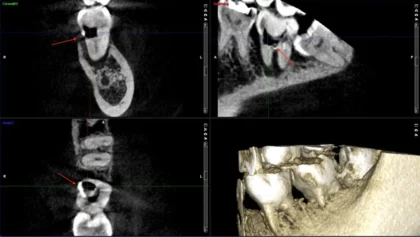

当院にご紹介でいらっしゃった患者さんで、左下の歯の痛みで他院で治療を受けていた患者さんです。当院でレントゲンを撮ると、親知らずの手前の歯の神経の治療を受けていました。レントゲン写真をみると大きく穴が空いており、なおかつ親知らずの影響もあり歯周病にもなっていた為、かなり状況が悪い事をお伝えして、治療方法をいくつか提示したところ、親知らずを矯正で状態の悪い歯の位置に移動させる事になりました。CTも撮影してご説明しました。

CTはレントゲンでは判りにくい部分を視覚的に患者さんに説明できるので、患者さんがイメージしやすく、当院ではインプラントや根の治療で活用しています。